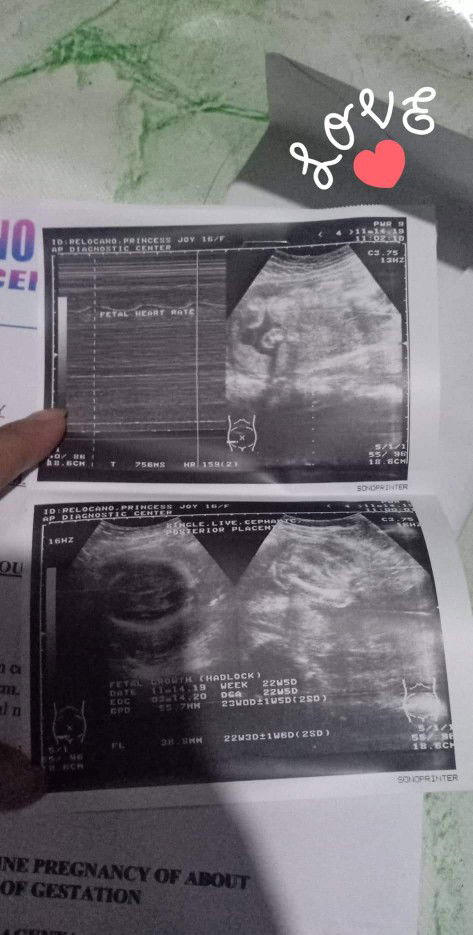

normal lg poba ano po sa tingin nyo girl or boy naka talikod po ksi eh

Hindi naman kita. Ikaw na din nagsabi na nakatalikod. Pa ultrasound ka nalang ulit